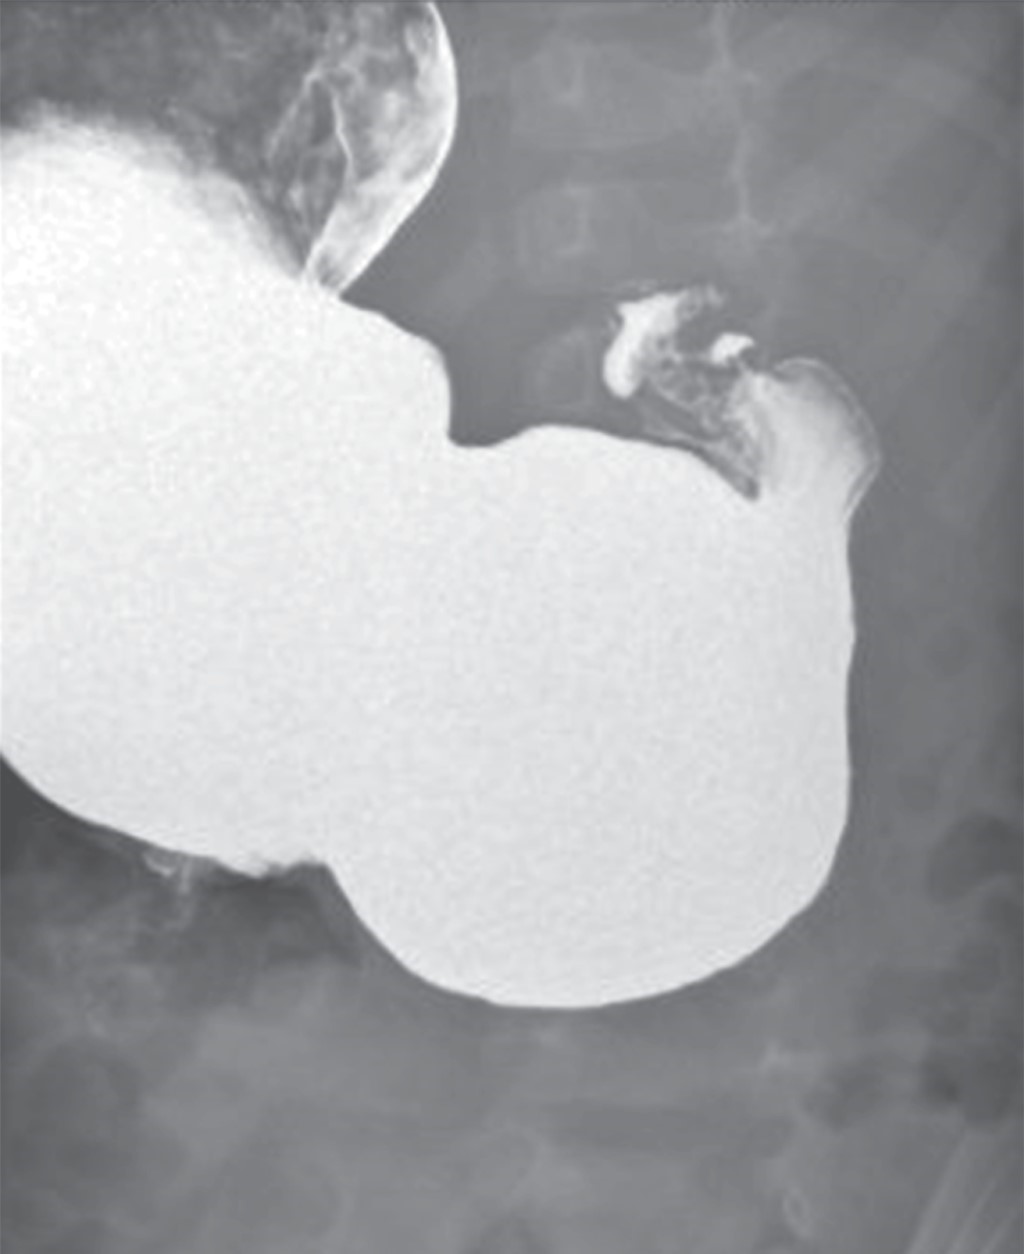

Figure 2